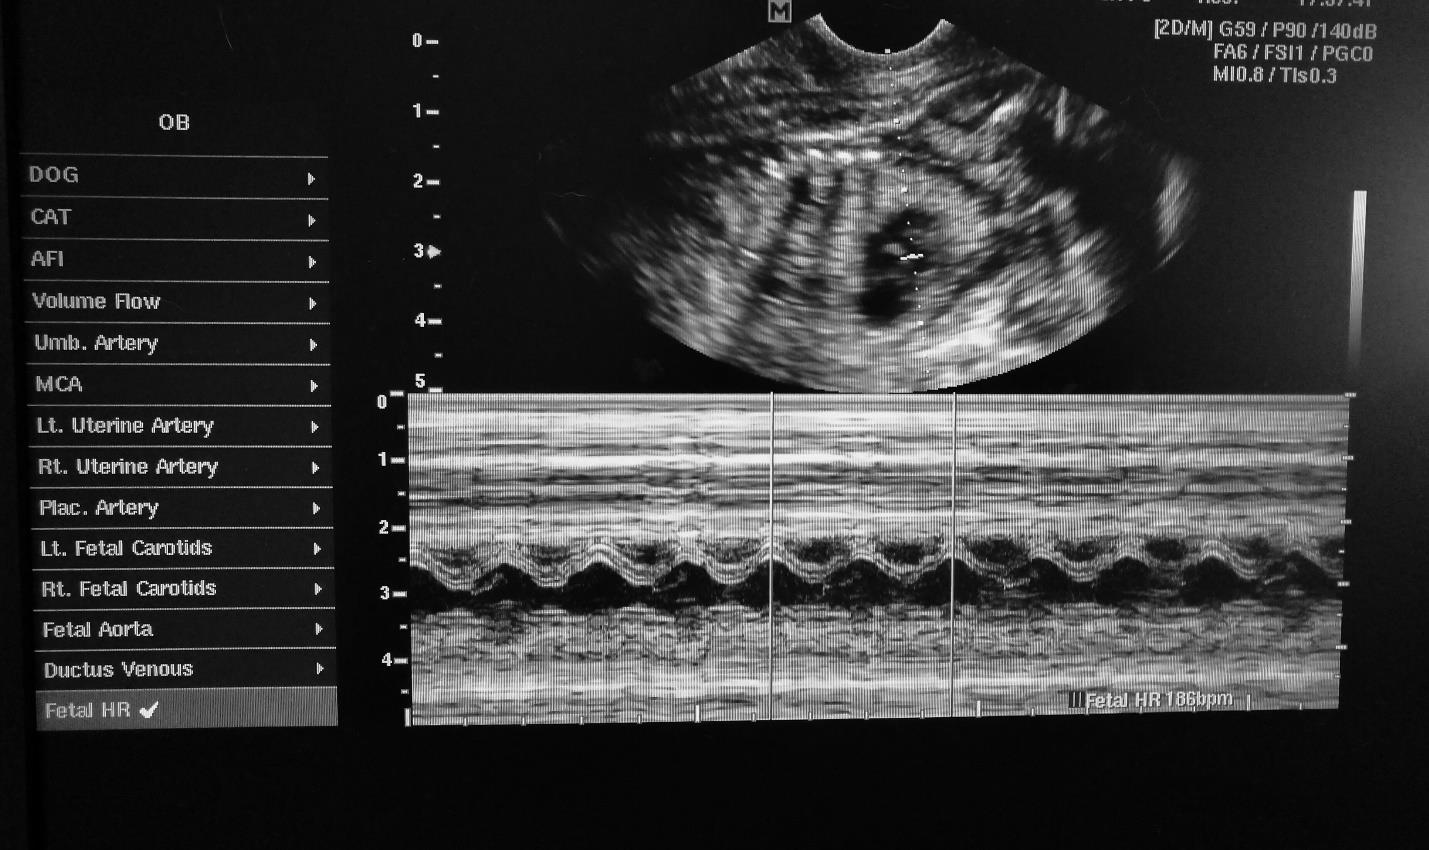

Our pet ultrasound services is a non-invasive procedure which is used for a variety of reasons including the most common which is checking for pregnancy in your dog or cat. It is entirely safe and painless, often carried out in just a few minutes from start to finish. All the information is openly displayed on a monitor which we share with the pet owner in realtime.

In the UK, pet ultrasound is commonly used for pregnancy checks in animals. Veterinarians use ultrasound technology to detect the presence of developing fetuses in a pregnant pet's uterus. This non-invasive and painless procedure allows for a clear visualisation of the embryos, helping to confirm pregnancy and estimate the number of puppies or kittens expected.

Ultrasound can also be used to monitor the health and growth of the fetus throughout the pregnancy. It is an essential tool in providing accurate and timely information about the reproductive status of pets, ensuring proper care and management during the pregnancy period.